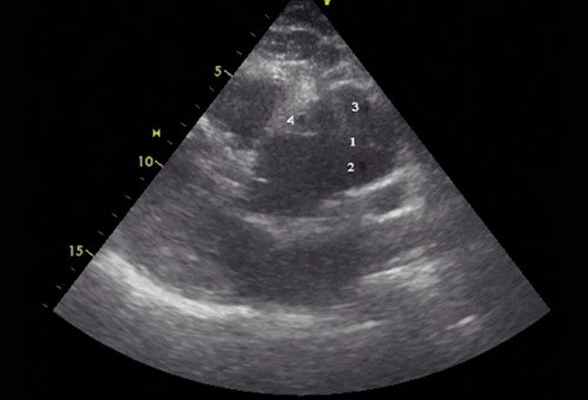

Рис. 2. Эхокардиограмма больного Ж. Парастернальная позиция по длинной оси с фокусом на восходящий отдел аорты.

1 - отслоенная интима аорты, 2 - истинный канал аорты, 3 - ложный канал аорты, 4 - тромботические массы в слепом участке ложного канала аорты.

Помимо гипертрофии миокарда левого желудочка, склеротически измененных створок аортального клапана и наличия его недостаточности I степени, обращало на себя внимание расширение восходящего отдела аорты до 4,5-5,1 см (на различных уровнях) (рис. 1). Исследование средних отделов восходящей аорты (рис. 2) позволяло выявить нитевидную, невыраженно флотирующую структуру, расположенную по передней стенке аорты, формирующую истинный и ложный каналы аорты, которые более детально верифицировались в режиме ЦДК (рис. 3). В слепом участке ложного канала определялись тромботические массы. При исследовании из супрастернального доступа в области дистального отдела восходящей аорты и ее дуги лоцировался участок отслоения интимы (рис. 4). В остальных отделах аорты, доступных для визуализации, патологии выявлено не было. Таким образом, ультразвуковое исследование сердца позволило диагностировать расслаивающую аневризму восходящего отдела и дуги аорты (тип II по De Bakey). Проведенная МСКТ подтвердила данный диагноз (рис. 5).